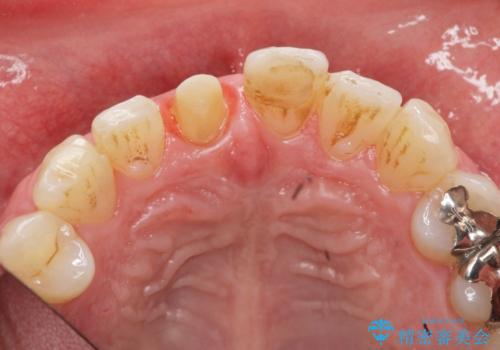

前歯の変色を改善 オールセラミック治療

感染の疑われる根管内に対し再度根管治療を行い、セラミッククラウンを作製することで審美性の回復します。

目立つ前歯の審美性が改善したことで見た目を気にせず笑えるようになった。との嬉しい感想をいただくことができました。